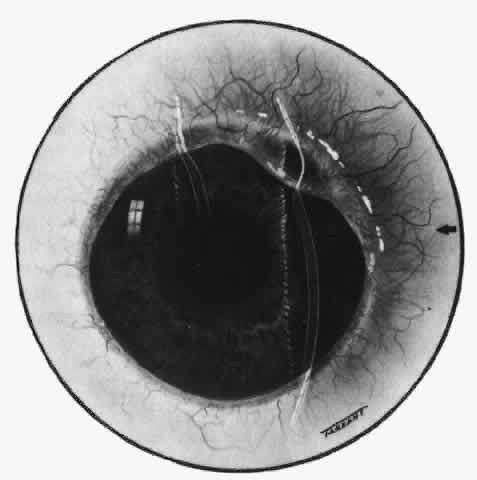

The characteristic features of necrotizing scleritis on fluorescein angiography are hypoperfusion and, eventually, nonperfusion of the vascular networks (Figs. 40 through 43).26 The initial changes are on the venous side of the capillary network; the transit time of the dye increases even if the eye is red and congested. If the disease process persists or has been present for a long time, thrombosis and permanent vaso-occlusive changes occur. These vessels (or the occluded capillary network) are bypassed by the opening of anastomotic channels. New vessels in a granuloma give rise to deep intrascleral leakage of dye (see Fig. 43). Conjunctival and episcleral involvement by the destructive change is late but is always preceded by vaso-occlusive changes that can sometimes be detected with use of the red-free light on the slit lamp (Figs. 44 and 45).

Fig. 40. Early necrotizing scleritis. There is characteristic yellow discoloration of the sclera underlying the conjunctiva at a point of necrosis. In this instance a small filament of tissue has penetrated the conjunctiva.

Fig. 41. Late stage of fluorescein angiogram adjacent to the site of necrosis in the same patient as in Figure 40. Although the eye is uniformly congested, the area near the necrosis shows vascular shutdown, whereas the rest of the conjunctiva and episclera is normally perfused.

Fig. 42. Late arterial phase of fluorescein angiogram in a patient with necrotizing scleritis. All the vessels except the main trunk and the vessels around the limbal perforating vessels are occluded and remain unperfused throughout the angiogram.

Fig. 43. Late venous phase of angiogram of a patient with necrotizing scleritis showing late deep leakage from vessels on the surface of the sclera and leakage of the capillary network at the limbus and the vessels draining it, together with poor or absent perfusion of the remaining vessels.